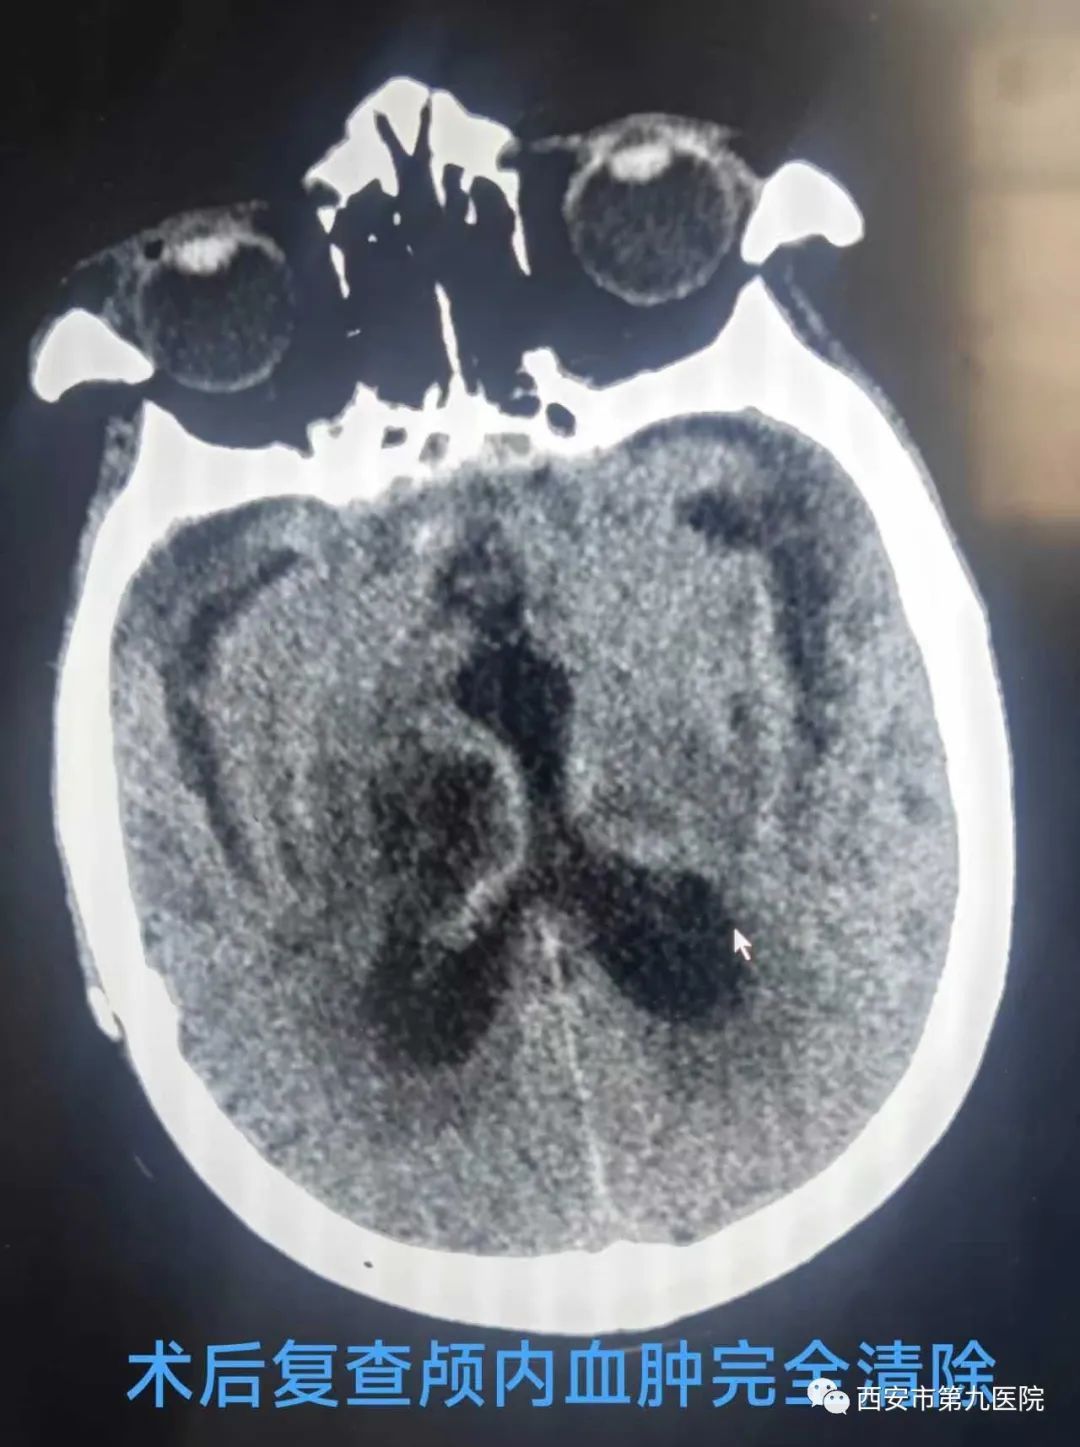

微创手术相比传统手术有创伤小,时间短,术后恢复快等优点,但也提出更高的要求,因为无法像传统开颅手术一样可以直视出血点,一旦术中出血将对病人造成更大的伤害,不过九院神经外科开展的CT引导下微创脑内血肿清除术可以在术中由CT实时定位,不但可以最大程度的避免损伤其他血管,还可以精准定位出血部位,更有效的清除血肿。刘晓勇主任医师带领蒋帅、赵英男医师、经过1个小时紧张的手术,老人脑袋里致命的血肿被清除了大半,少量残余血肿也在三天内由引流管引出,老人暂时转危为安。